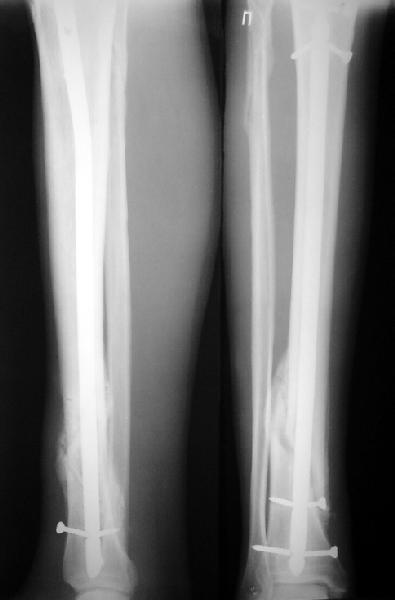

JOM> Вы не послали послеоперационный снимок, поэтому трудно судить о

JOM> состоянии редукции после операции.

А зачем о ней судить - речь ведь не об этом. Мы, помнится, обсуждали возможность ранней нагрузки после остеосинтеза.

JOM> Установка с медиальной стороны гвоздя в области дистального фрагмента

JOM> дополнительного шурупа помогло бы Вам репонировать и удержать перелом

Да, конечно. Но сочли, что и достигнутое положение приемлемо. Тем более, для non-compliant и low demanding пациента.

А если вспомнить лечение аналогичных повреждений функциональными брэйсами (Sarmiento), там рентгенограммы могут быть еще менее привлекательными, однако результаты вполне приемлемы.

JOM> Кстати, если можно пошлите послеоперационный снимок.

Ok. А также и следующий, в 3 месяца.

Это наглядная демонстрация возможности ранней полной нагрузки при нестабильном по оси повреждении, причем не в самых благоприятных механических условиях - при плохом сопоставлении, со слабым фиксатором.